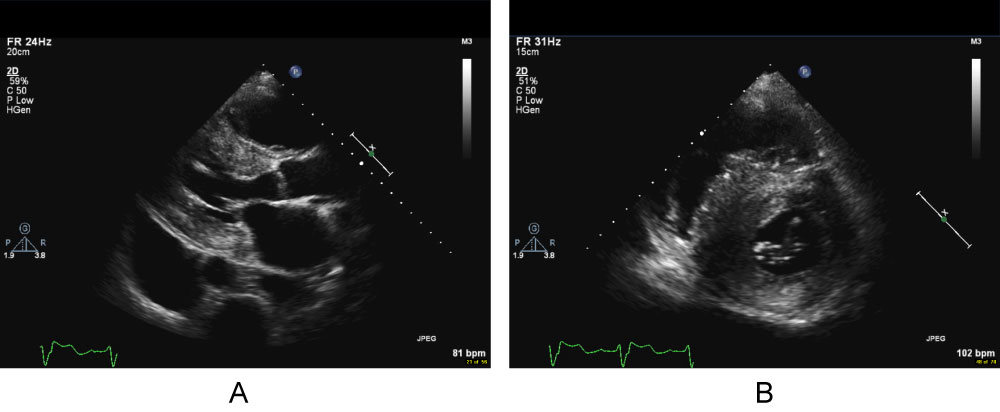

A screening transthoracic echo at presentation to our center showed a severely increased interventricular septal thickness of 22 mm, grade 1 diastolic dysfunction pattern, systolic anterior motion of the mitral valve with a left ventricular outflow gradient of 46 mmHg, mild mitral regurgitation, and left ventricular ejection fraction (LVEF) of 50% (Figure 1, Video 1A, Video 1B and Video 1C). Further testing demonstrated a serum Brain Natriuretic Peptide of 1388 pg/mL (normal < 53.2 pg/ml). An electrocardiogram showed normal sinus rhythm, left ventricular hypertrophy, left anterior fascicular block, and ST-T waves changes consistent with repolarization abnormality (Figure 2). Cardiac MRI (CMR) revealed a septal thickness of 19 mm and left ventricular mass of 532 g, LVEF of 59%, right ventricular ejection fraction of 52%, and a single focus of delayed enhancement within the anterior wall in a pattern that did not suggest an infiltrative cardiomyopathy (Figure 3 and Video 2). These CMR and echocardiographic findings confirmed a diagnosis of hypertrophic cardiomyopathy (HCM).

Video 1A: Video clips of the transthoracic echocardiogram (TTE) obtained during initial evaluation at the Boston University Amyloidosis Center. A) Parasternal long-axis;

Video 1B: B) Parasternal short-axis;

Video 1C: C) And apical four-chamber (C) Views reveal severely increased LV wall thickness with asymmetric septal hypertrophy, preserved LV systolic function and systolic anterior motion (SAM) of the anterior mitral valve leaflet.